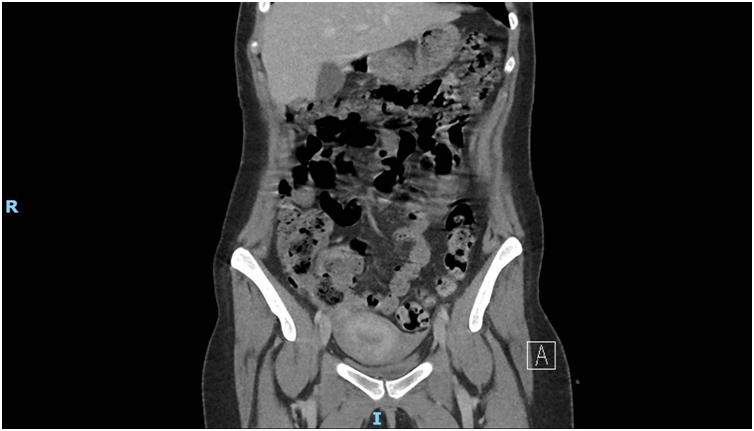

Presacral cystic lesions are rare and diagnostically challenging due to their nonspecific symptoms and deep anatomical location. We report a case of a young woman with a recurrently infected pre-coccygeal cyst, first identified following an emergency Caesarean section in 2020. Over the next five years, the lesion increased in size likely exacerbated by hormonal changes during successive pregnancies, resulting in chronic pelvic pain, neurological symptoms, and cutaneous fistulisation.

Imaging via MRI and CT demonstrated a complex, encapsulated lesion with peripheral enhancement and restricted diffusion. Multidisciplinary evaluation suggested a congenital epidermoid or duplication cyst. Given the absence of malignancy and surgical complexity, a conservative management strategy was adopted.

Figure 3: Figure 3 Duplication cyst 2020 Coronal plane